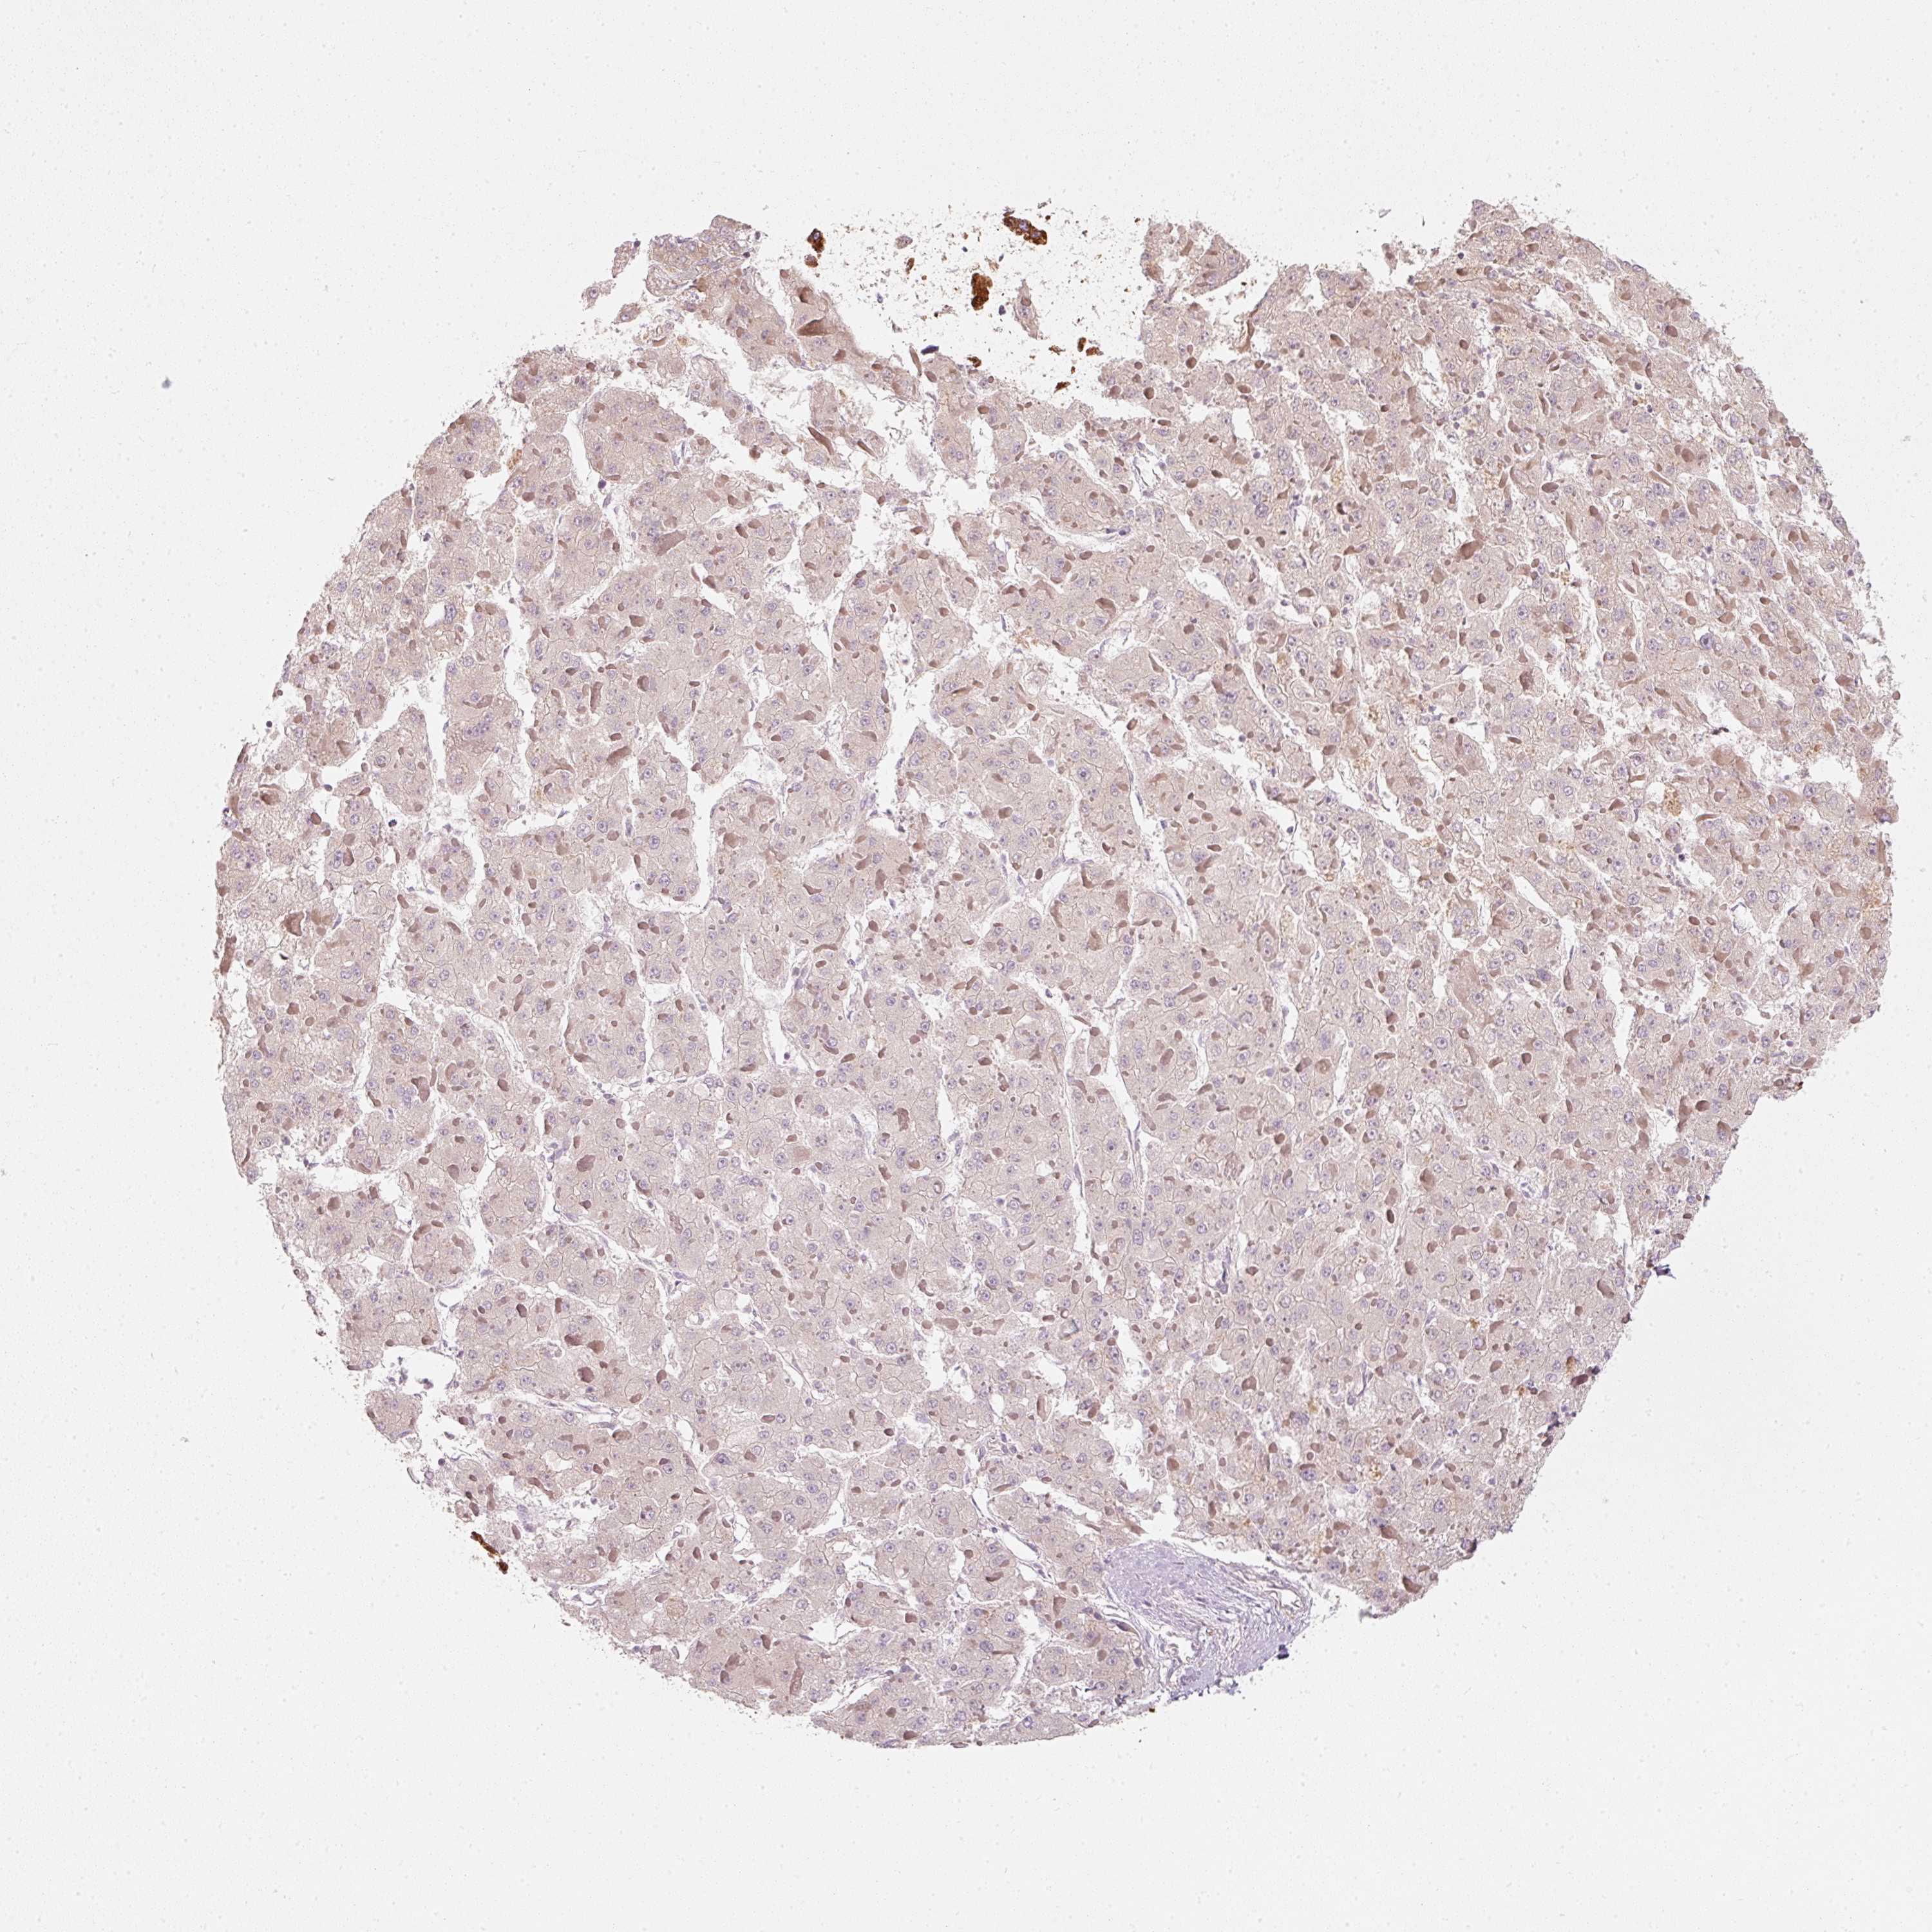

LIVER CANCER - Protein expressioni

A mouse-over function shows sample information and annotation data. Click on an image to view it in a full screen mode. Samples can be filtered based on level of antibody staining by selecting one or several of the following categories: high, medium, low and not detected. The assay and annotation is described here.

Antibody stainingi

Antibody staining in the annotated cell types in the current human tissue is reported as not detected, low, medium, or high, based on conventional immunohistochemistry profiling in selected tissues. This score is based on the combination of the staining intensity and fraction of stained cells.

Each image is clickable and will lead to virtual microscopy that enables deeper exploration of all samples and also displays staining intensity scores, fraction scores and subcellular localization as well as patient and tissue information for each sample.

Antibody HPA054422

Antibody HPA060360

Staining

High

Medium

Low

Not detected

Intensity

Strong

Moderate

Weak

Negative

Quantity

>75%

75%-25%

<25%

None

Location

Nuclear

Cytoplasmic/membranous

Cytoplasmic/membranous,nuclear

Carcinoma, Hepatocellular, NOS

Cholangiocarcinoma